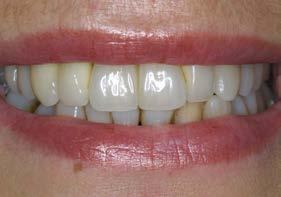

Una vez finalizados los postes, se prueban antes del cementado de las coronas para verificar que la zona ceramizada genere un margen gingival estético, evitando la exposición de metal incluso ante una posible recesión gingival leve. Asimismo, el hombro de la restauración se sitúa a nivel yuxtagingival, con el fin de evitar la presencia de cemento subgingival durante el cementado. Posteriormente se realiza la prueba de coronas (Figura 9) y su colocación definitiva (Figuras 10–12).

En una visión ampliada de la zona anterosuperior se aprecia la adecuada adaptación de los tejidos blandos a las coronas, lograda mediante la provisionalización y el diseño de pónticos y pilares que favorecen un contorno gingival armónico (Figuras 13 y 15).

Figuras 10 y 11. Prótesis definitiva colocada en la paciente.